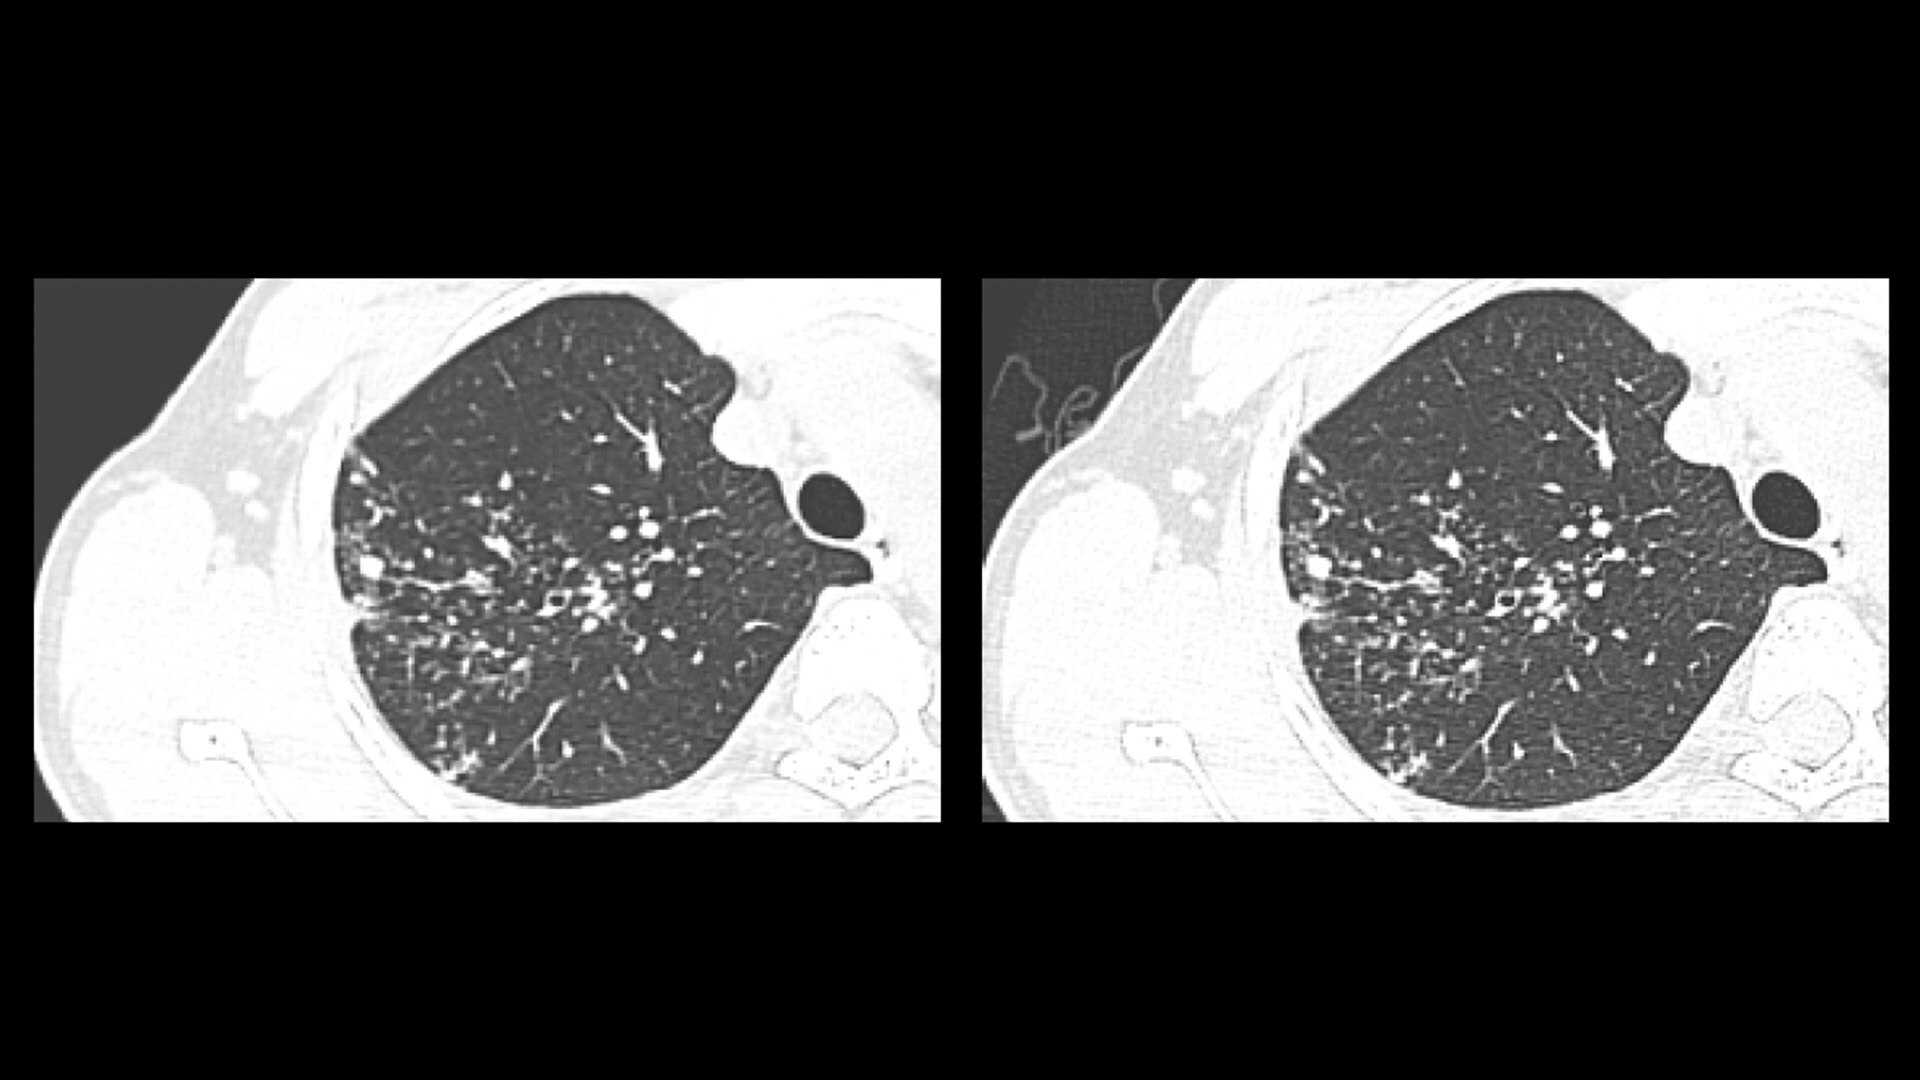

At the heart of Revolution Advance is a high-performance, reliable imaging chain with 42 kW of generator power, a 3.5 MHU X-ray tube and integrated detectors that reduce signal-to-noise by 20%2. This is paired with our smart, dose-reducing reconstruction applications like ASiR2, which can provide up to 40% lower dose while maintaining high image quality2.

When it comes to imaging more challenging cases, such as neuro, oncology or pediatric patients, VISR3. (Volumetric Image Space Reconstruction) reduces noise without impacting image resolution. This means less dose for the patient while maintaining the high-image quality you need for more accurate diagnoses.